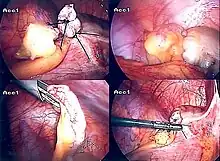

Laparoscopic appendectomy

Laparoscopic appendectomy was introduced in 1983 and has become an increasingly prevalent intervention for acute appendicitis.[88] This surgical procedure consists of making three to four incisions in the abdomen, each 0.25 to 0.5 inches (6.4 to 12.7 mm) long. This type of appendectomy is made by inserting a special surgical tool called a laparoscope into one of the incisions. The laparoscope is connected to a monitor outside the person's body, and it is designed to help the surgeon to inspect the infected area in the abdomen. The other two incisions are made for the specific removal of the appendix by using surgical instruments. Laparoscopic surgery requires general anesthesia, and it can last up to two hours. Laparoscopic appendectomy has several advantages over open appendectomy, including a shorter post-operative recovery, less post-operative pain, and lower superficial surgical site infection rate. However, the occurrence of an intra-abdominal abscess is almost three times more prevalent in laparoscopic appendectomy than open appendectomy.[89]